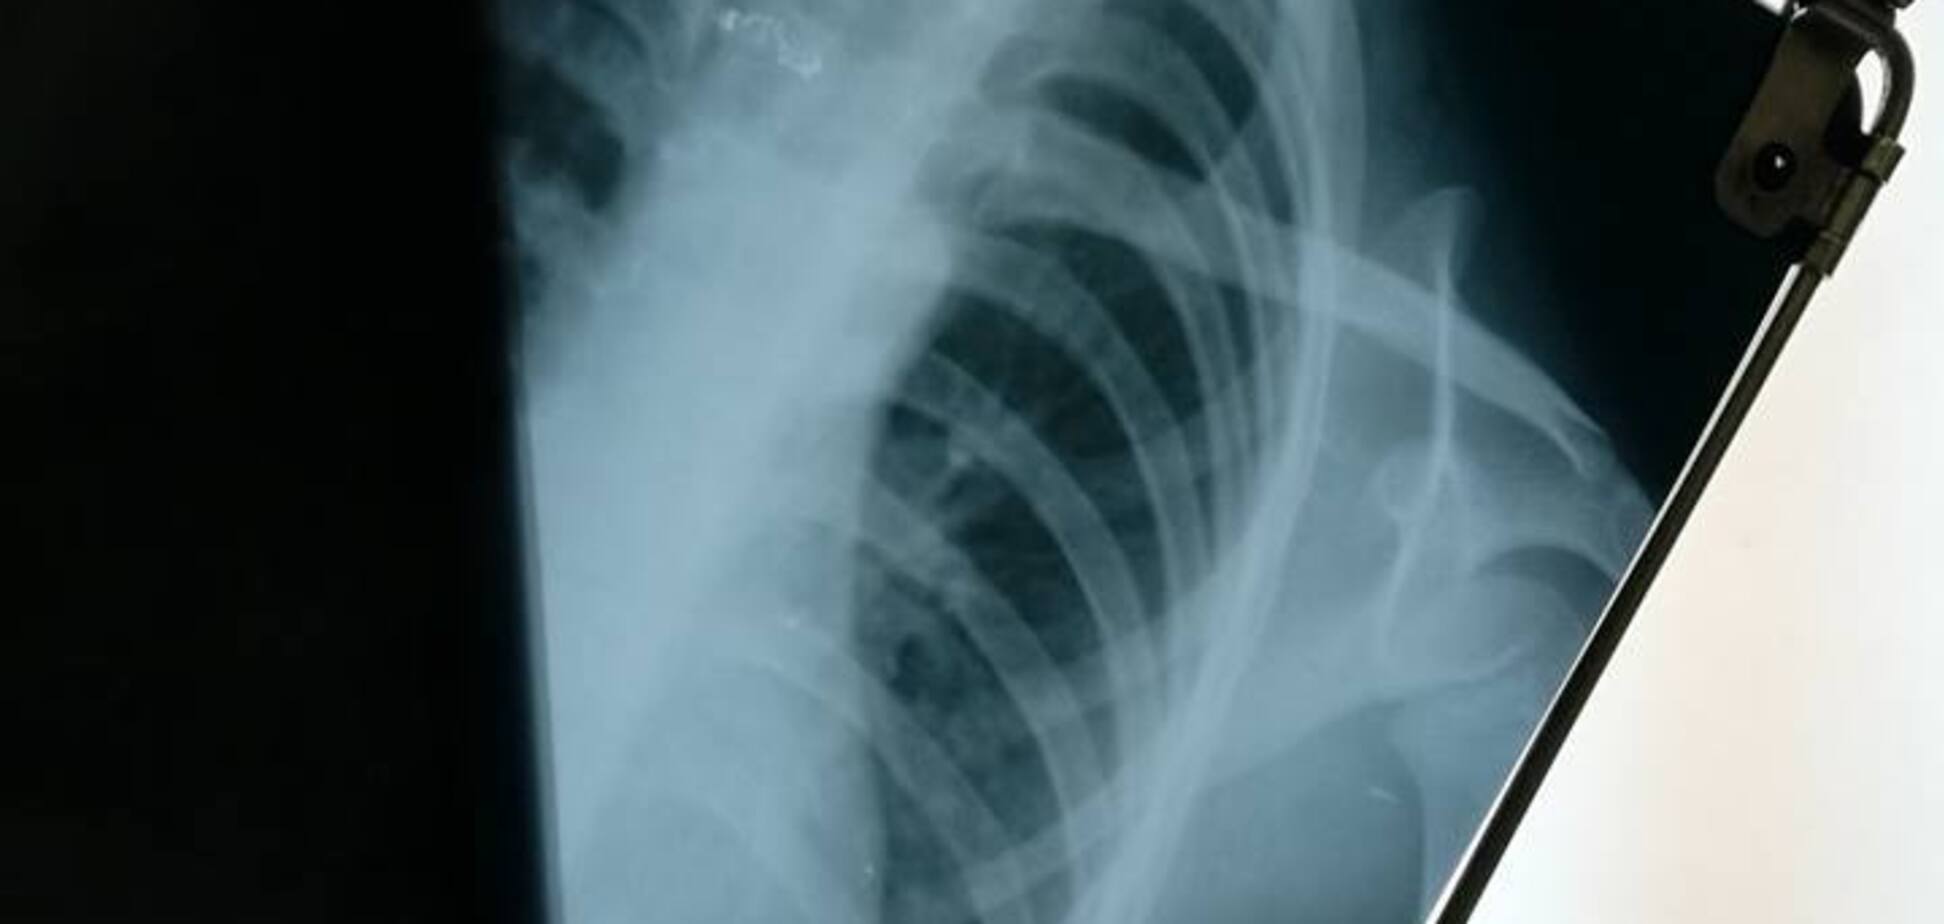

Он рассказал, что предмет был серого цвета, примерно 2-3 сантиметра в длину и он застрял у него чуть ниже шеи. Диагностика в больнице и рентген действительно указали на наличие инородного предмета в пищеводе.

Спустя несколько дней, 22 сентября, хирург из "Охматдета" подтвердил, что на первом рентгене видно инородное тело. Однако после того, как снимки переделали, оно перестало просматриваться. Видимая угроза для здоровья ребенка миновала, однако, по словам родителя, в саду не пытались выяснить причину происшествия или поинтересоваться состоянием воспитанника.